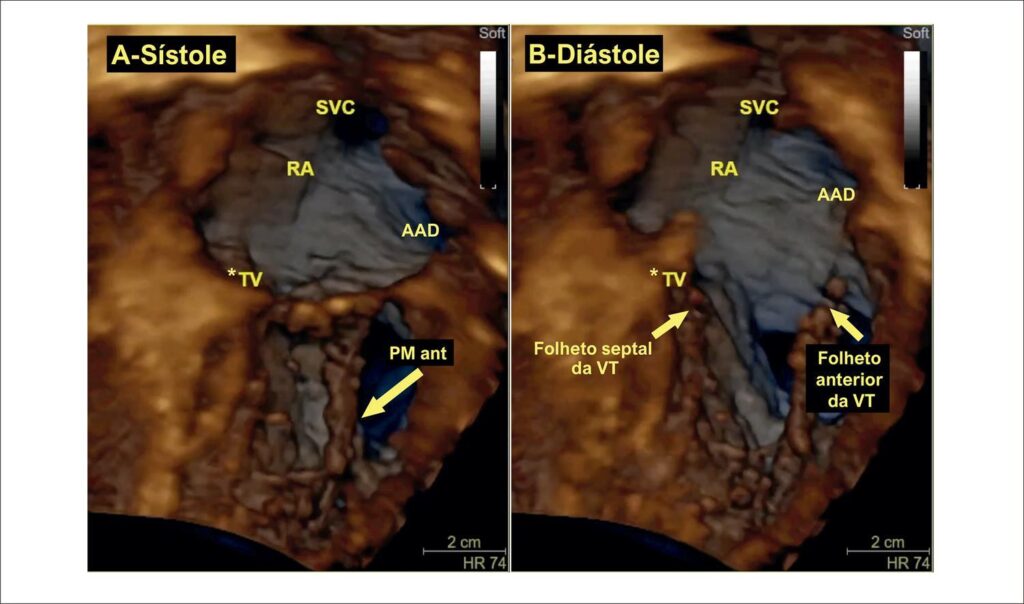

É difícil obter imagens da VT na ecocardiografia transesofágica pelos seguintes motivos: 1) os folhetos são muito mais finos em comparação com os folhetos mitrais, com maior variabilidade anatômica; 2) é uma estrutura anterior, distante do esôfago, com sombra acústica do esqueleto fibroso do coração; e 3) não pode ser alinhado com a sonda esofágica para adquirir imagens en face e requer o uso de resolução lateral. Essas restrições podem limitar a capacidade da ecocardiografia transesofágica tradicional de avaliar a TV, tornando-se necessário complementar a avaliação com janelas especiais do esôfago inferior e transgástricas. Diferentemente de outras valvas cardíacas, as imagens da VT obtidas por ecocardiografia transtorácica costumam ter melhor resolução do que as imagens obtidas pela ecocardiografia transesofágica. Embora todos os protocolos comecem com a avaliação bidimensional (2D) da VT, a ecocardiografia tridimensional (3D) desempenha um papel importante na avaliação das doenças da VT, não apenas por sua capacidade de retratar com precisão a anatomia da valva e do aparelho subvalvar, mas também pela sua acurácia na quantificação dos volumes e da função do ventrículo direito (VD) e do átrio direito, bem como da análise funcional da disfunção valvar, especialmente para graduar a RT e avaliar a dinâmica do anel tricúspide por meio de software dedicado. Todas essas informações são de importância inigualável para o manejo do paciente e o planejamento pré-procedimento em abordagens cirúrgicas e transcateter.